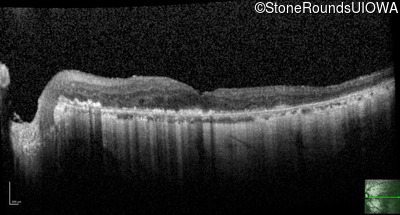

This 81 year old man began using a flashlight to read menus in his 40's. At age 75 his ophthalmologist noticed abnormal fundus findings and referred him to a retina specialist.

Diagnosis & molecular findings

| Late Onset Retinal Dystrophy | C1QTNF5 | Ser163Arg AGC>AGA | AD |

Disease:

Gene:

Allele 1:

Ser163Arg AGC>AGA

Inheritance:

AD